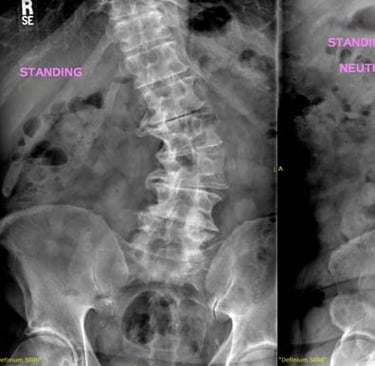

في العمود الفقري السليم، تُشكِّل الفقرات عمودًا رأسيًا مع انحناءات طبيعية خفيفة من الأمام إلى الخلف. أمّا في حالة الجنف، فإن العمود الفقري ينحني أيضًا بشكل جانبي في المستوى الأمامي، وقد يصاحبه دوران، مما قد يؤدي إلى عدم التناسق في وضعية الجسم والمظهر العام.

ويُؤخَذ تشخيص الجنف عادةً بعين الاعتبار عندما يتجاوز انحناء العمود الفقري حدًا معيّنًا في الفحوصات التصويرية، وغالبًا ما يتم قياس ذلك باستخدام زاوية كوب (Cobb angle) في صور الأشعة السينية.

يبدأ تشخيص الجنف بتقييم سريري يشمل أخذ تاريخ صحي مفصّل وفحصًا بدنيًا شاملًا. وقد يلاحظ الممارس الصحي وجود عدم تماثل في مستوى الكتفين أو الوركين أو الخصر، أو اختلافًا في وضعية الجسم. وتُستخدم الفحوصات التصويرية، مثل الأشعة السينية، لتأكيد وجود الانحناء وقياس درجة شدّته.